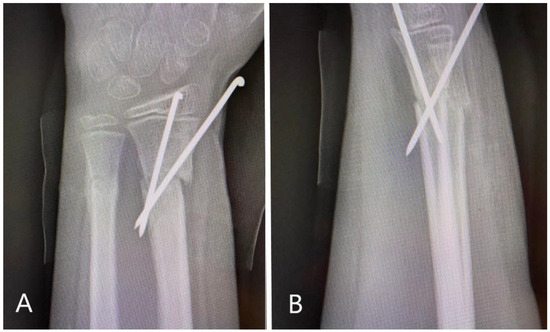

A plain X-ray at initial presentation confirmed a fracture of the distal third of the radius with important displacement and volar angulation >30° (Figure 1A). At presentation, orthopedic reduction was the first gesture but this failed by orthopedic means with a non-successful conservative attempt.

Figure 1. Radiological images obtained at presentation: AP (antero-posterior) (A) and oblique (B) view of the distal forearm, demonstrating important volar displacement of the radial fracture, and greenstick fracture of the distal ulna with dorsal angulation. Also, the fracture presented with a rotational displacement of the distal radial fragment together with the radiocarpal complex.